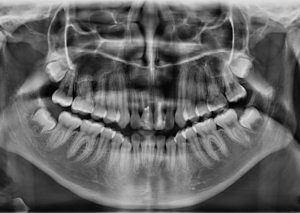

Paciente femeninos de 40 años acude a la sede IDM – Miraflores para realizarse una tomografía de campo reducido y descartar una fractura. Radiografia Panorámica